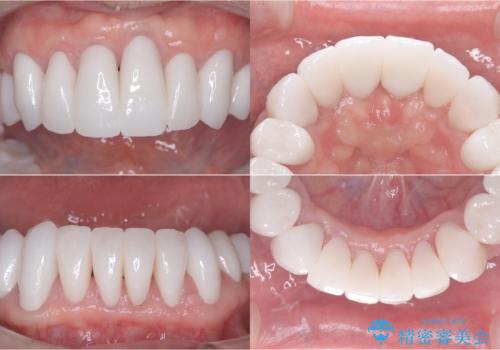

- 強い酸によって歯が広範囲にわたって侵食され、「歯がボロボロになった」と主訴に来院されました。詳細な診査の結果、重度の酸蝕症と診断。失われた歯質や咬み合わせの崩壊が著しいことから、単一の治療では対応が困難と判断し、矯正治療、インプラント治療、セラミック治療を組み合わせた総合的な治療計画を立案しました。矯正治療後に最終的にセラミックを用いて機能性と審美性を回復。患者様と綿密な話し合いを重ね、長期的な口腔内の健康維持を見据えた最適な治療を行いました。

酸蝕症の原因に関しては、医科のほうで解決済みでしたので、失われた機能、審美性の回復のため矯正治療によって歯並びと咬み合わせのバランスを整えセラミックによる修復を行ました。

保存できないと判断した歯は抜歯しインプラントにて治療をおこなっています。

矯正後、歯肉の形態不良のため、歯周外科を行い連続性を獲得しています。